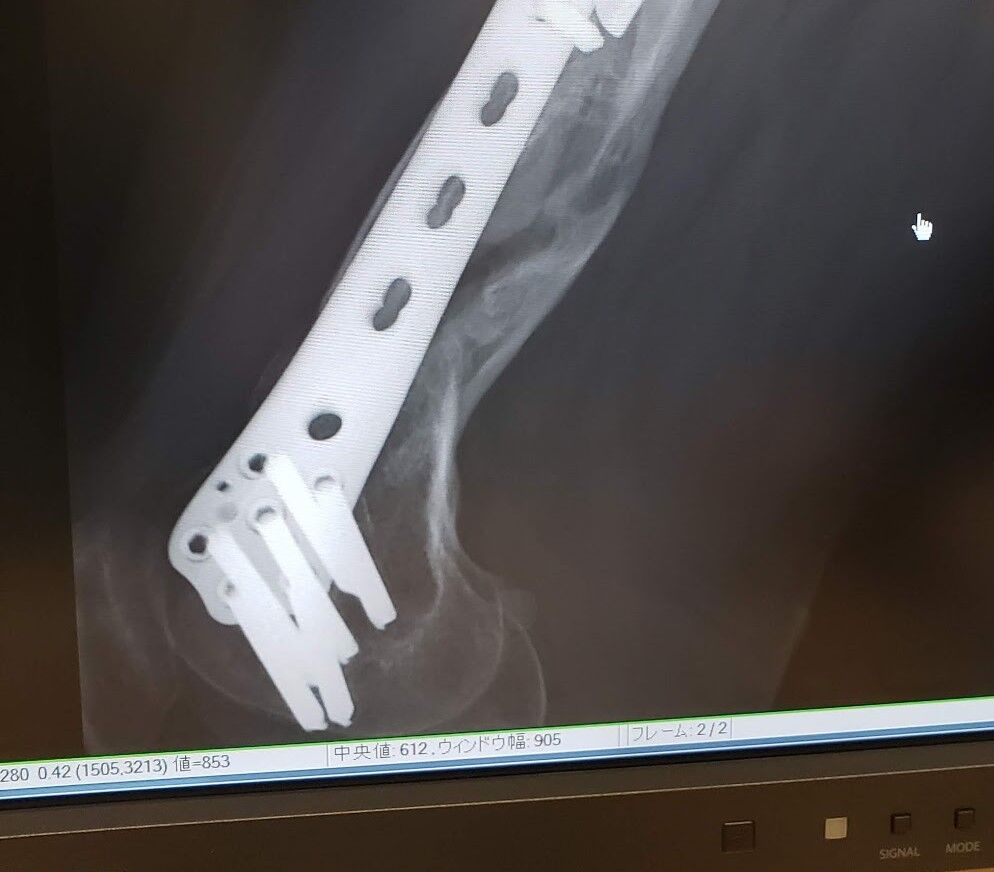

で、病院でレントゲン見たら、、、ボルトが折れてるwwしかも結構プレートが動いてる、変だと思った〜納得!

正直レースが近ければそのままほっておくんですが、この際プレートを抜いてもらおうかと思っています。

大腿骨下部の部分はまだスカスカなんで必要なら腰から骨を出して骨移植になると思います。